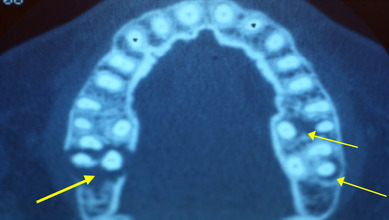

Souvent les dents présentant les lésions tissulaires les plus avancées compilent un plus grand nombre de facteurs occlusaux aggravants tels que la présence de facettes d’usure, l’altération des courbes de compensation occlusales (Spee et Wilson) ou l’intensité des contacts dento-dentaires lors des mouvements

fonctionnels.

Ainsi, plus de 75 % des dents présentant des poches profondes et une perte d’attache cumulent deux à trois facteurs occlusaux aggravants. Réciproquement, les dents les moins atteintes présentent entre aucun et un seul facteur occlusal aggravant.